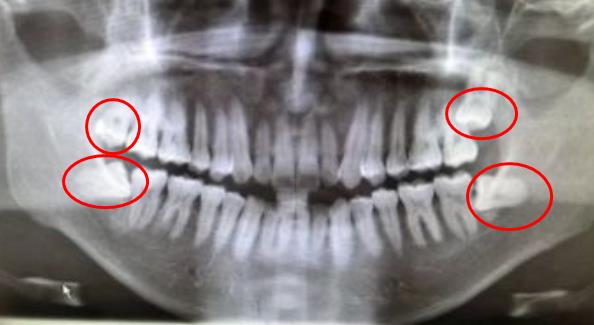

紅圈內(nei) 的4顆牙齒為(wei) 智齒

還有大家需要先確定自己有幾顆智齒,一般需要先到醫院拍片查看智齒數量。一般來說,智齒有0——4顆,不同的**口內(nei) 智齒的數量不一致,有可能沒有,也有可能有3顆、4顆,所以數量越多,而且都需要拔除的話,那智齒拔牙的價(jia) 格自然就要高一些,這也是沒辦法的事情。